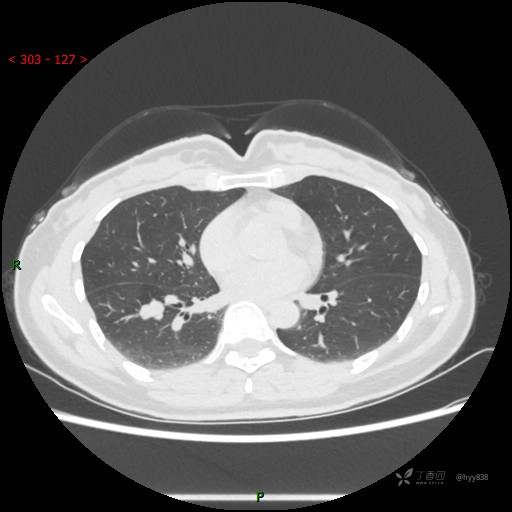

辅助检查:CT

静脉期

CT值